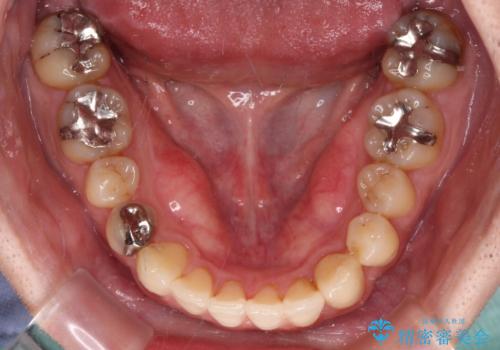

- デコボコした前歯をセラミックできれいに揃えたいとのことで来院された患者様です。

歯を削って整えることは簡単ですが、健全な歯を削って後悔してからでは遅いため、矯正治療を提案しました。

はじめは矯正治療の期間が長いことに悩んでいらっしゃいましたが、ある程度整えば満足するだろうとのことで、インビザラインにて矯正治療を行うこととしました。

左上の犬歯が欠損しているため、正中の位置や奥歯の咬み合わせが理想的にならない点を了承していただきました。